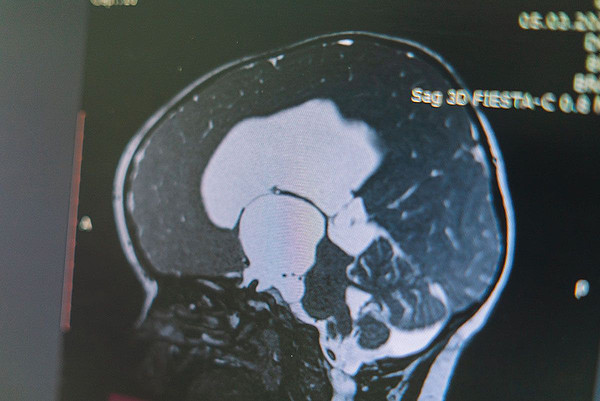

IMG_20221215_105257_858IMG_20221215_105258_024

IMG_20221215_105258_024.